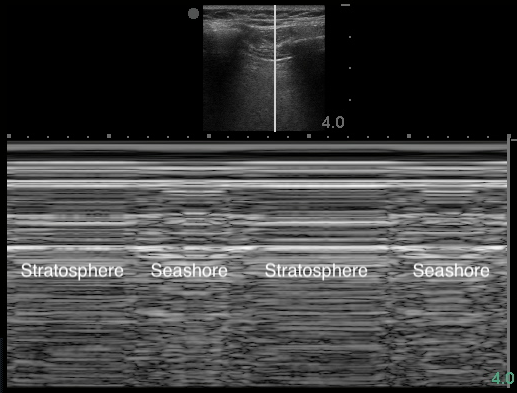

- Figure 16. Stratosphere sign in M-mode

- Air within pleural space scatters the sound waves. The stationary parietal pleura attached to the chest wall is still visualized, but the visceral pleura is not.

- Highly sensitive but not specific for PTX11,58

- Other etiologies: mainstem intubation, COPD blebs,62 prior pleurodesis, apnea, severe atelectasis or consolidation, ARDS, pulmonary contusion, severe fibrosis, phrenic nerve palsy63